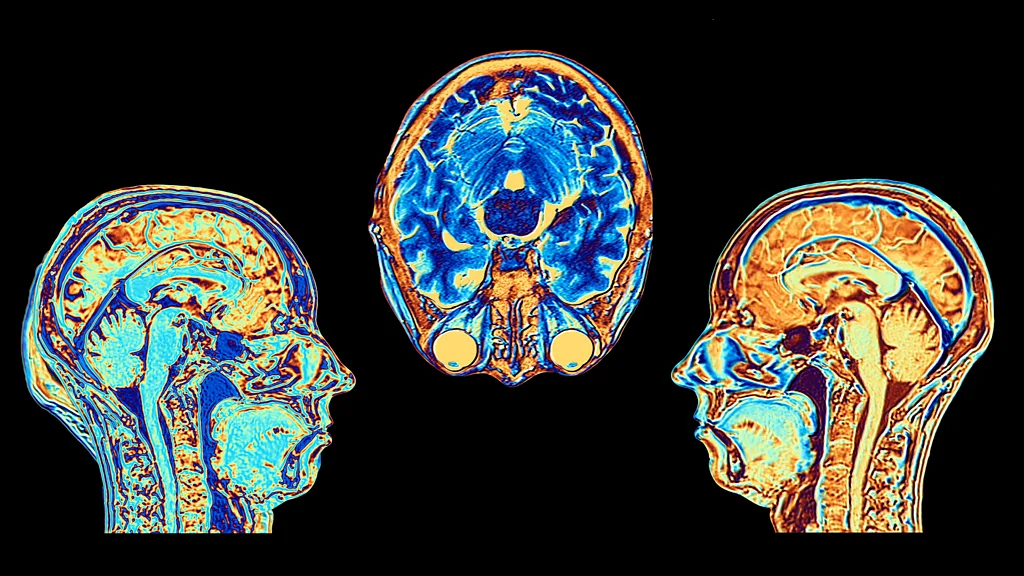

Foto: Serenity Strull/BBC/Getty Images